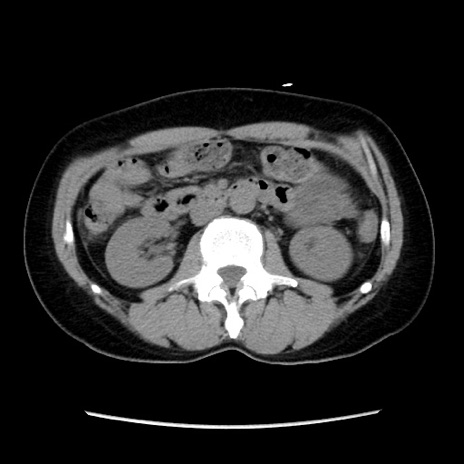

症例10(横断像)

【症例】 50歳代女性

【主訴】 腹痛

【現病歴】前日生レバーを食べた。今朝に排便あり。 昼前に突然発症の腹痛を生じ、当院救急外来を受診した。

【身体所見】 意識清明、腹部:平坦、軟、下腹部やや左を中心に圧痛・反跳痛あり、筋性防御あり

【データ】WBC 7800、CRP 0.07